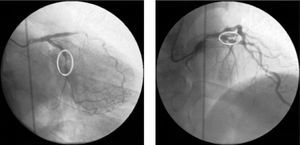

Angiographic control of the last lesion treated (proximal LAD) showed a good angiographic result at the stent implantation site, but a new pre-stent lesion was now visible in the proximal circumflex artery (Fig. 3).

Immediately afterwards there was a drop in arterial blood pressure and the angiogram revealed other new lesions and reduced flow throughout the coronary tree. The patient went into cardiogenic shock and the coronary angiogram showed retention of contrast at various points of the left coronary artery, principally intrastent, and TIMI 0 distal flow (Fig. 4A). Basic and advanced life support maneuvers were begun, a temporary pacing lead was implanted (due to complete atrioventricular block followed by ventricular asystole) and an intra-aortic balloon pump was inserted.

There were various possible causes for this situation including coronary dissection and no-reflow phenomenon, but the most likely in view of the clinical and angiographic context was severe diffuse vasospasm of the coronary tree; intracoronary verapamil was accordingly administered while the patient was still undergoing resuscitation maneuvers and in electromechanical dissociation. This, together with the rest of the pharmacological arsenal and resuscitation efforts, was successful in obtaining TIMI 3 flow (Fig. 4B), sinus rhythm and a rise in blood pressure.